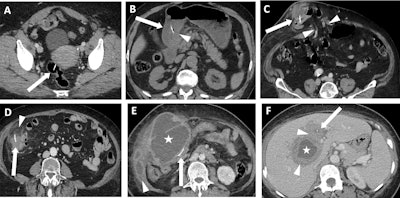

Various case examples of fishbone localization and related complications. (A) A fishbone (arrow) is visualized within the lumen of the rectum. The patient was asymptomatic, and no bowel wall thickening or adjacent fat stranding was observed, therefore this patient was excluded from analysis. (B) A fishbone (arrow) is impacted in the antral wall of the stomach, with no perforation but mild thickening of the antral wall (arrowhead). The patient presented with abdominal pain and inflammatory syndrome. (C) A fishbone (arrow) perforates the ileum, localised within an abdominal wall hernia (arrowheads). A fluid collection is forming at the site of perforation. (D) A fishbone (arrow) perforates the right colon, without pneumoperitoneum. Only epiploic fat stranding is seen (arrowhead). (E) A large epiploic fluid collection (star) is seen fistulizing into the abdominal wall (arrowhead). A fishbone (arrow) is visualized within the transverse colon. (F) The patient presented with a right liver lobe abscess (star) with hypodense infiltration (arrowhead) surrounding the collection and extending towards the hepatic hilum. A small linear foreign body, consistent with a fishbone (arrow), is seen within the liver.Ben Zitoun et al; EJR